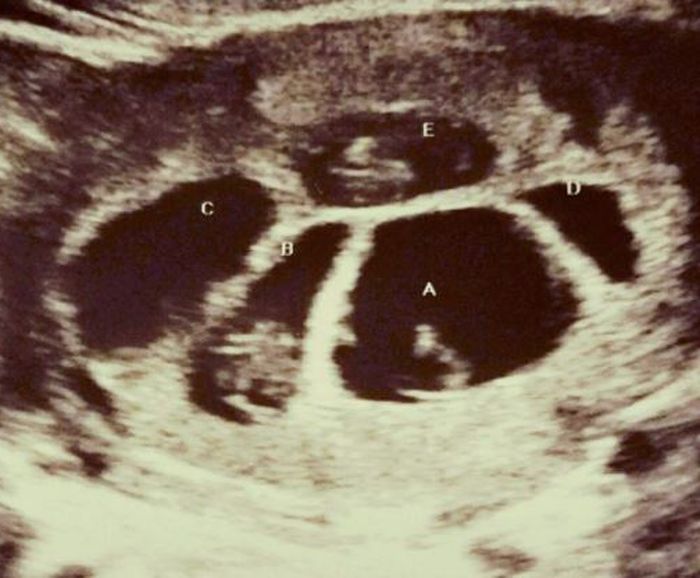

Hasil USG rahim Briana